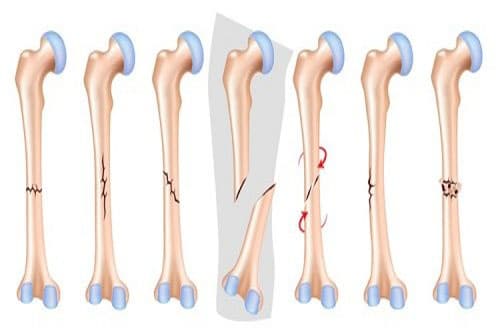

Gãy xương là gì? Biểu hiện và cách làm xương mau lành nhất

Gãy xương là gì? Nó có biểu hiện như thế nào và làm sao để làm xương mau lành nhất? Cùng tham khảo ngay thông tin chi tiết về bệnh gãy xương và giải pháp điều trị cũng như cách làm xương mau lành nhất qua bài viết dưới đây. 1. Gãy xương là gì? […]